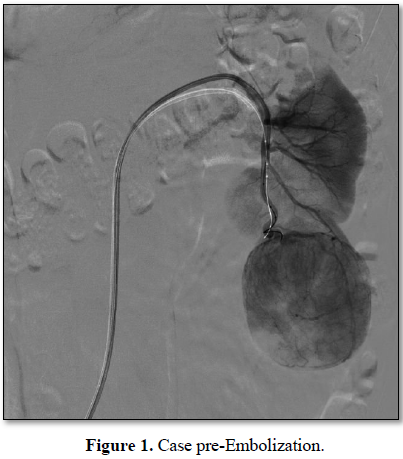

In this study we have chosen 3 patients and through the RENAL SCORE we have planned the procedure in a multidisciplinary team. The first patient is a 46 years old woman, with a tumor of 6.2 cm, entirely exophytic, localized on the lower pole of the left kidney. She has no significant comorbidity. She has been staged with TC chest-abdomen, without evidence of venous thrombus or metastasis (cT1b; N0; V0; M0). The second patient is a 64 years old woman, with a tumor of 4.1 cm, partially exophytic, localized on the superior pole of the right kidney. In anamnesis she has hypertension, obesity and hepatopathy HCV+. She has been staged with TC chest-abdomen, without evidence of venous thrombus or metastasis (cT1b; N0; V0; M0). The third patient is a 55 years old man, with a tumor of 4.8 cm, almost entirely exophytic and near to collecting system (5 mm), of the superior pole of the right kidney. In anamnesis he has only GERD. He has been staged with TC chest-abdomen, without evidence of venous thrombus or metastasis (cT1b; N0; V0; M0). At first renal arteriography is made to visualize the arterial vascularization, focused on the tumoral artery that is catheterized super selectively. The tumor and its artery is embolized with Onyx. The second time of the procedure performed is the RAPN.

In all patients the total operative time and the resection time of the tumor time are reduced compared to median of our center. Intraoperative bleeding is minimal and it isn’t necessary to isolate the vascular pedicle. In all procedures the time of ischemia is 0. The post-operative course has been regular (Clavien 0 in every patient). The tumor of patient 1 is a chromophobe cell renal carcinoma, the tumor of patient 2 is a papillary renal cell carcinoma type 1, the tumor of patient 3 is a clear cell renal carcinoma. In all patients’ surgical margins are negative. The complete description of the pre-operative, intraoperative and post-operative features is showed in Tables 1-3 and Figures 1 and 2.